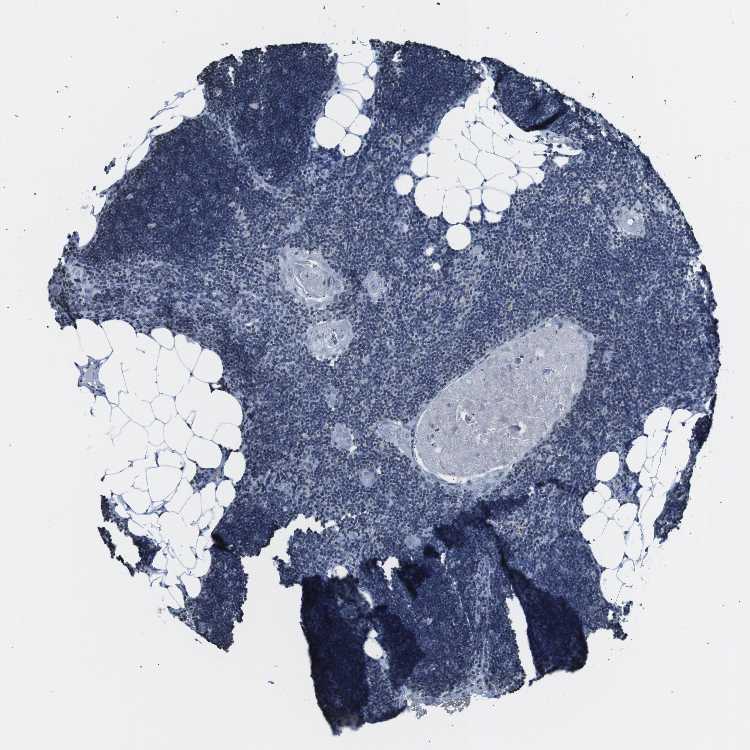

TISSUE PRIMARY DATA LYMPH NODE Show tissue menu

Lymph node

LYMPH NODE - Antibody stainingi

Antibody staining in the annotated cell types in the current human tissue is reported as not detected, low, medium, or high, based on conventional immunohistochemistry profiling in selected tissues. This score is based on the combination of the staining intensity and fraction of stained cells.

Each image is clickable and will lead to virtual microscopy that enables deeper exploration of all samples and also displays staining intensity scores, fraction scores and subcellular localization as well as patient and tissue information for each sample.

Antibody CAB016313

Germinal center cells Not detected

Non-germinal center cells Not detected